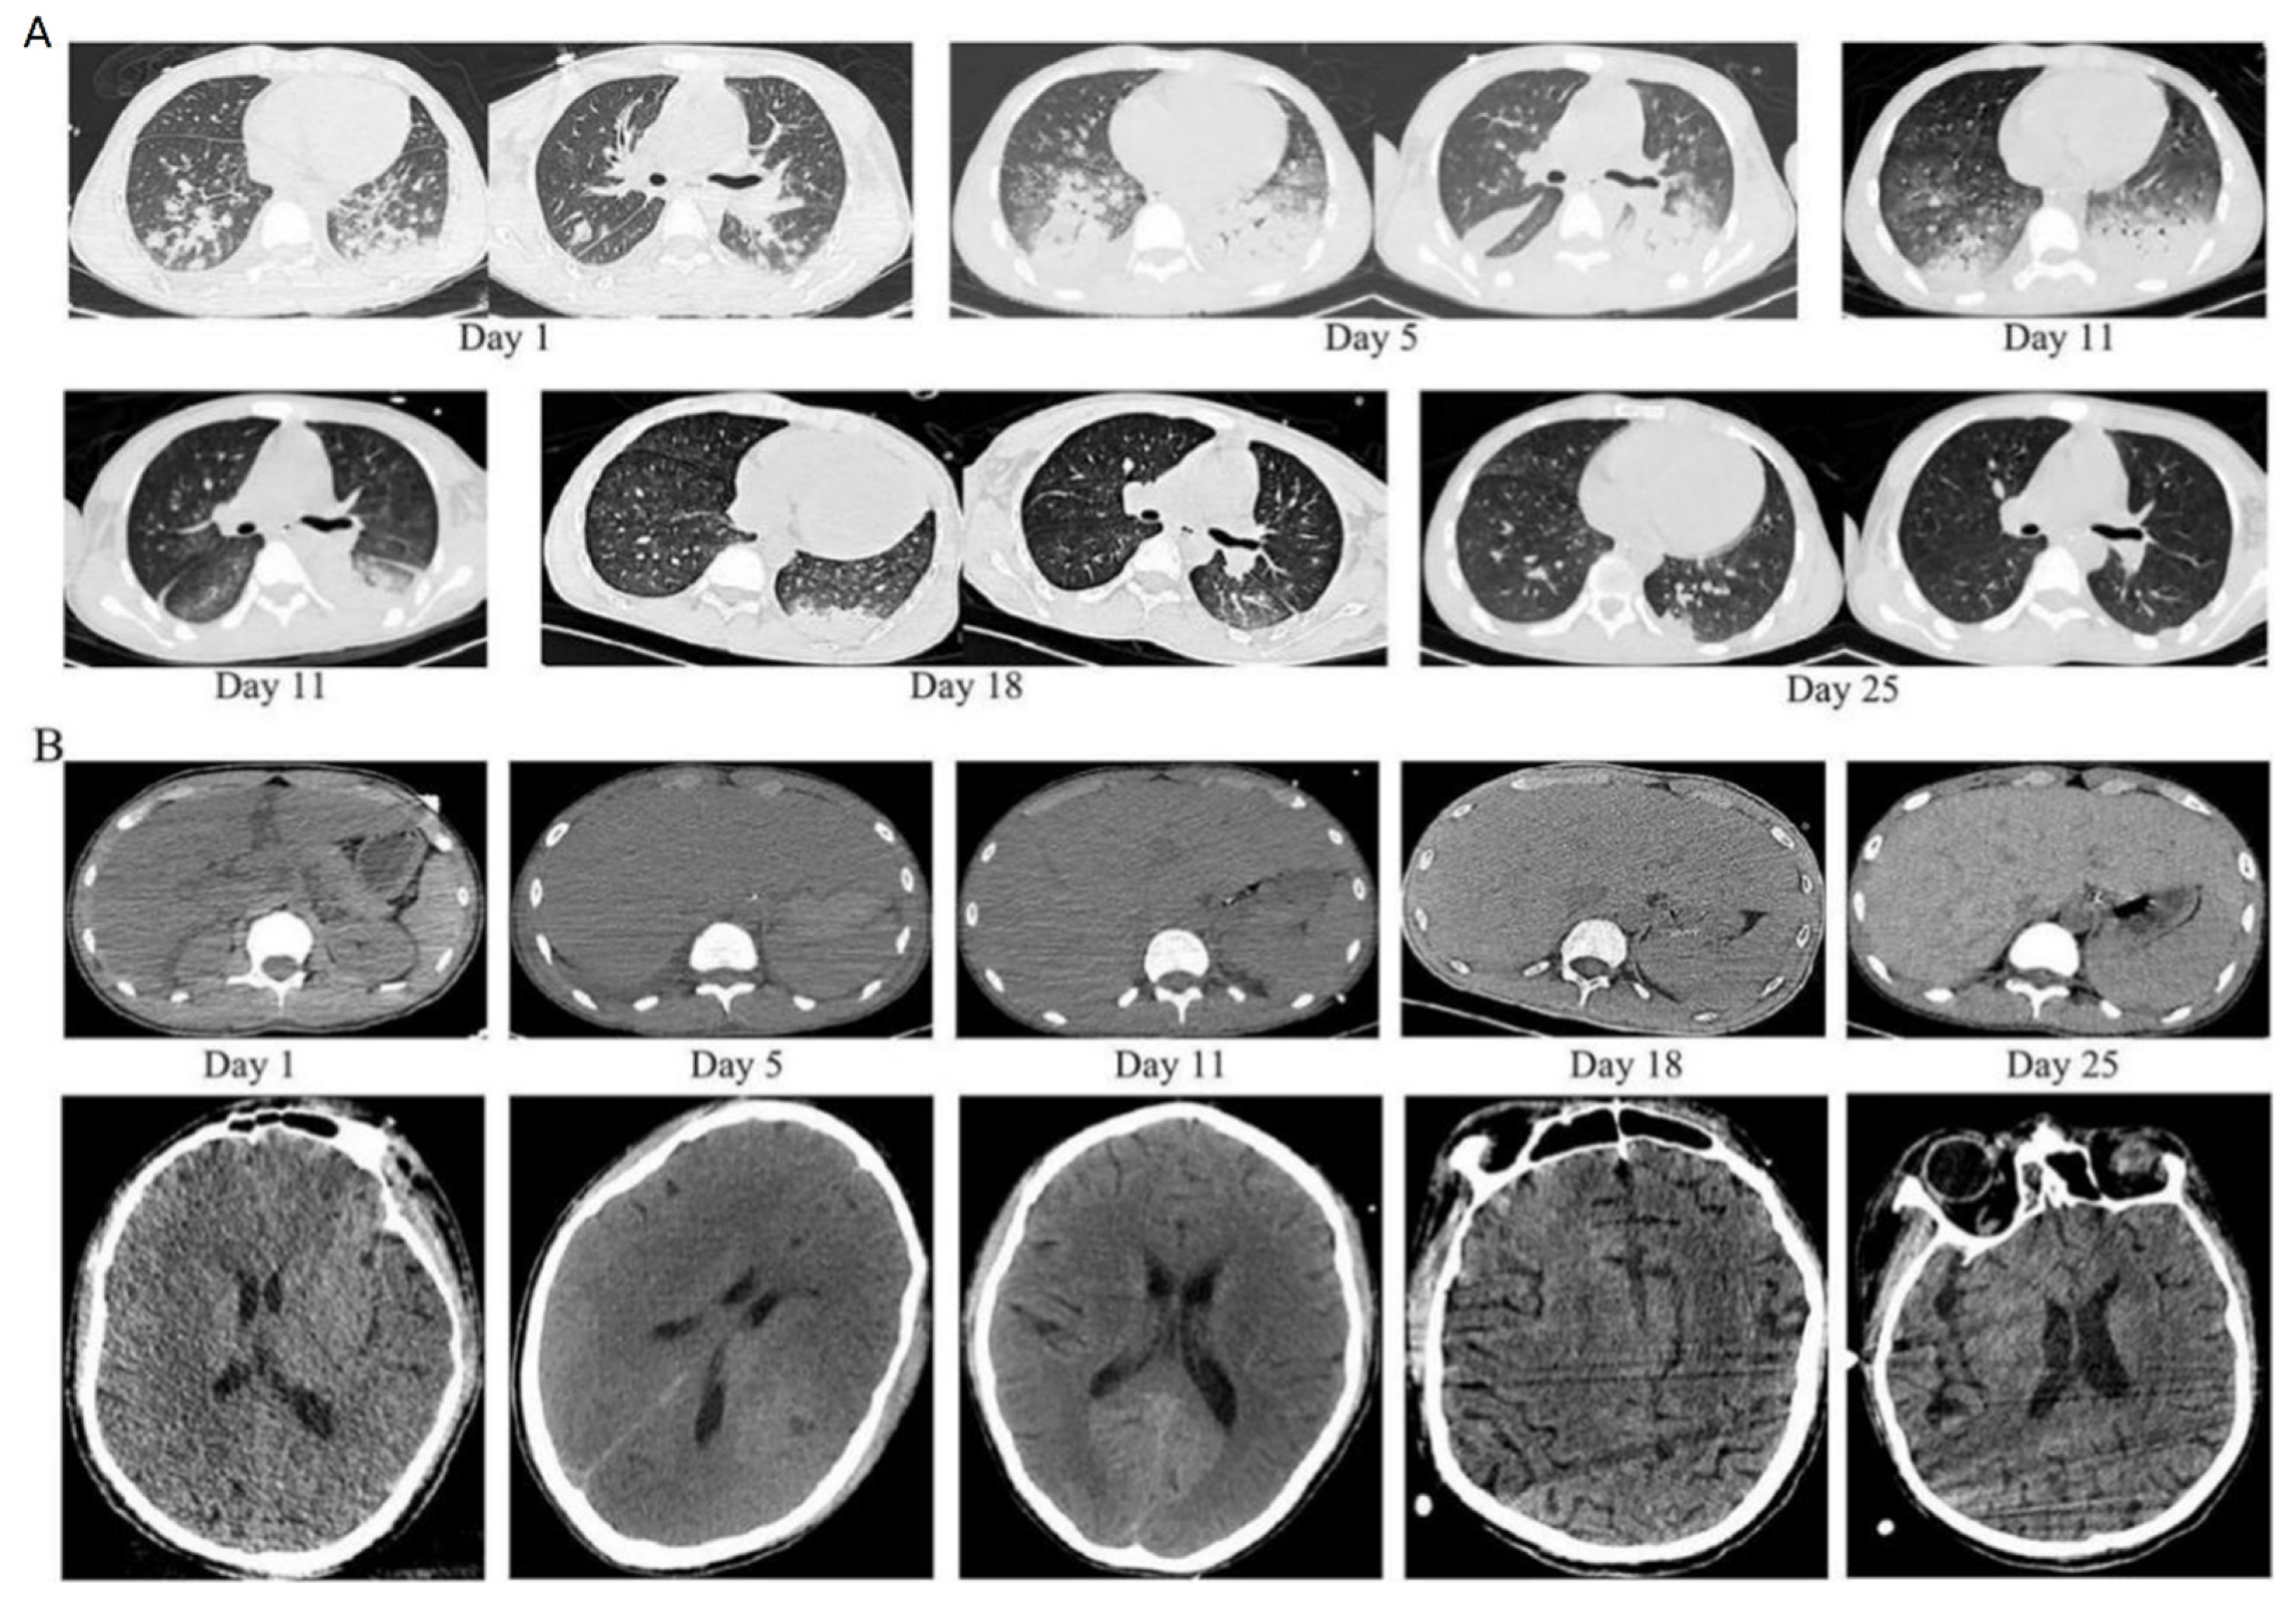

- The chest computed tomography (CT) scan showed inflammatory exudate and oedema in both lungs, bilateral pleural effusion, enlarged liver and spleen, and brain cell oedema (Figure 1).